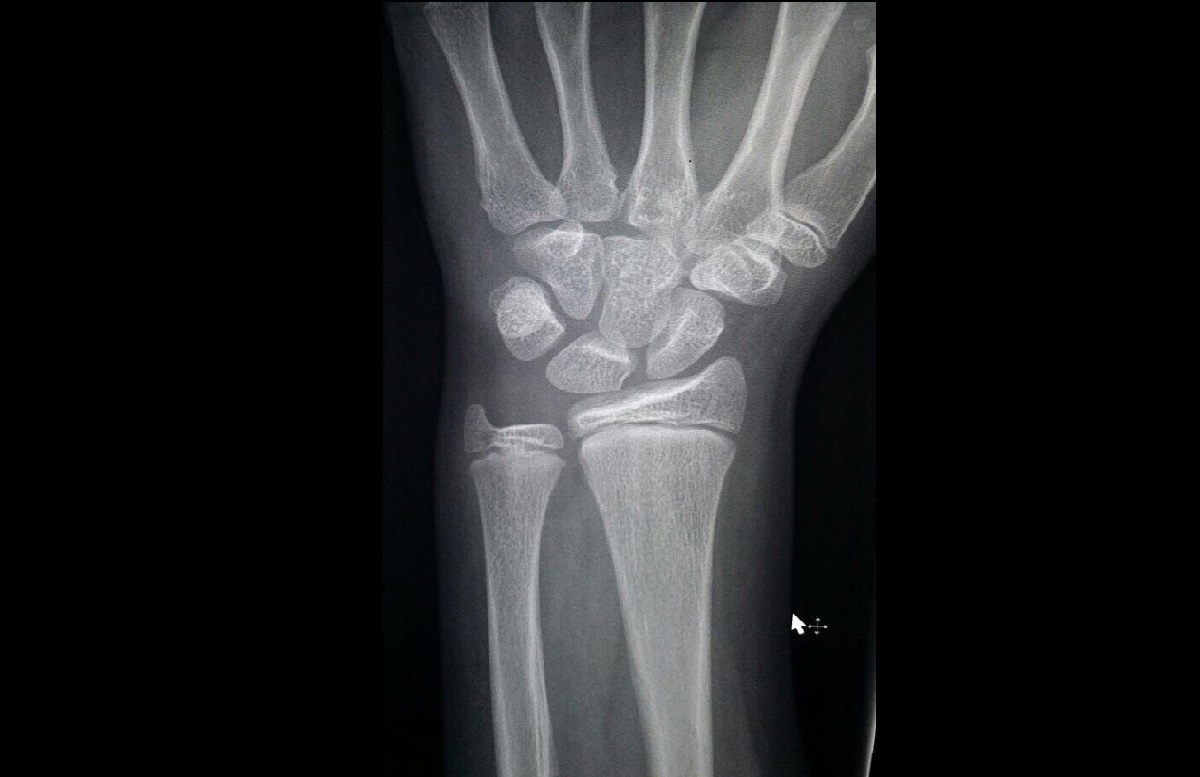

Torus Fracture X Ray . Cortical buckling at the medial aspect of both the distal radius metaphysis and distal ulnar metaphysis. Lustosa l, torus fracture of the radius. Torus fractures are a common paediatric injury involving the distal radius. Torus fractures, also known as buckle fractures, of the distal radius are a very common reason for presentation to emergency departments. Also, there may be a plastic deformation of an. Patients typically present following a fall onto. Subtle buckling of cortex is seen at the distal end of radius, seen as a small protuberance on the frontal view, imaging features are.